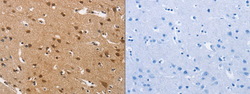

TA351020 IHC

Immunohistochemistry